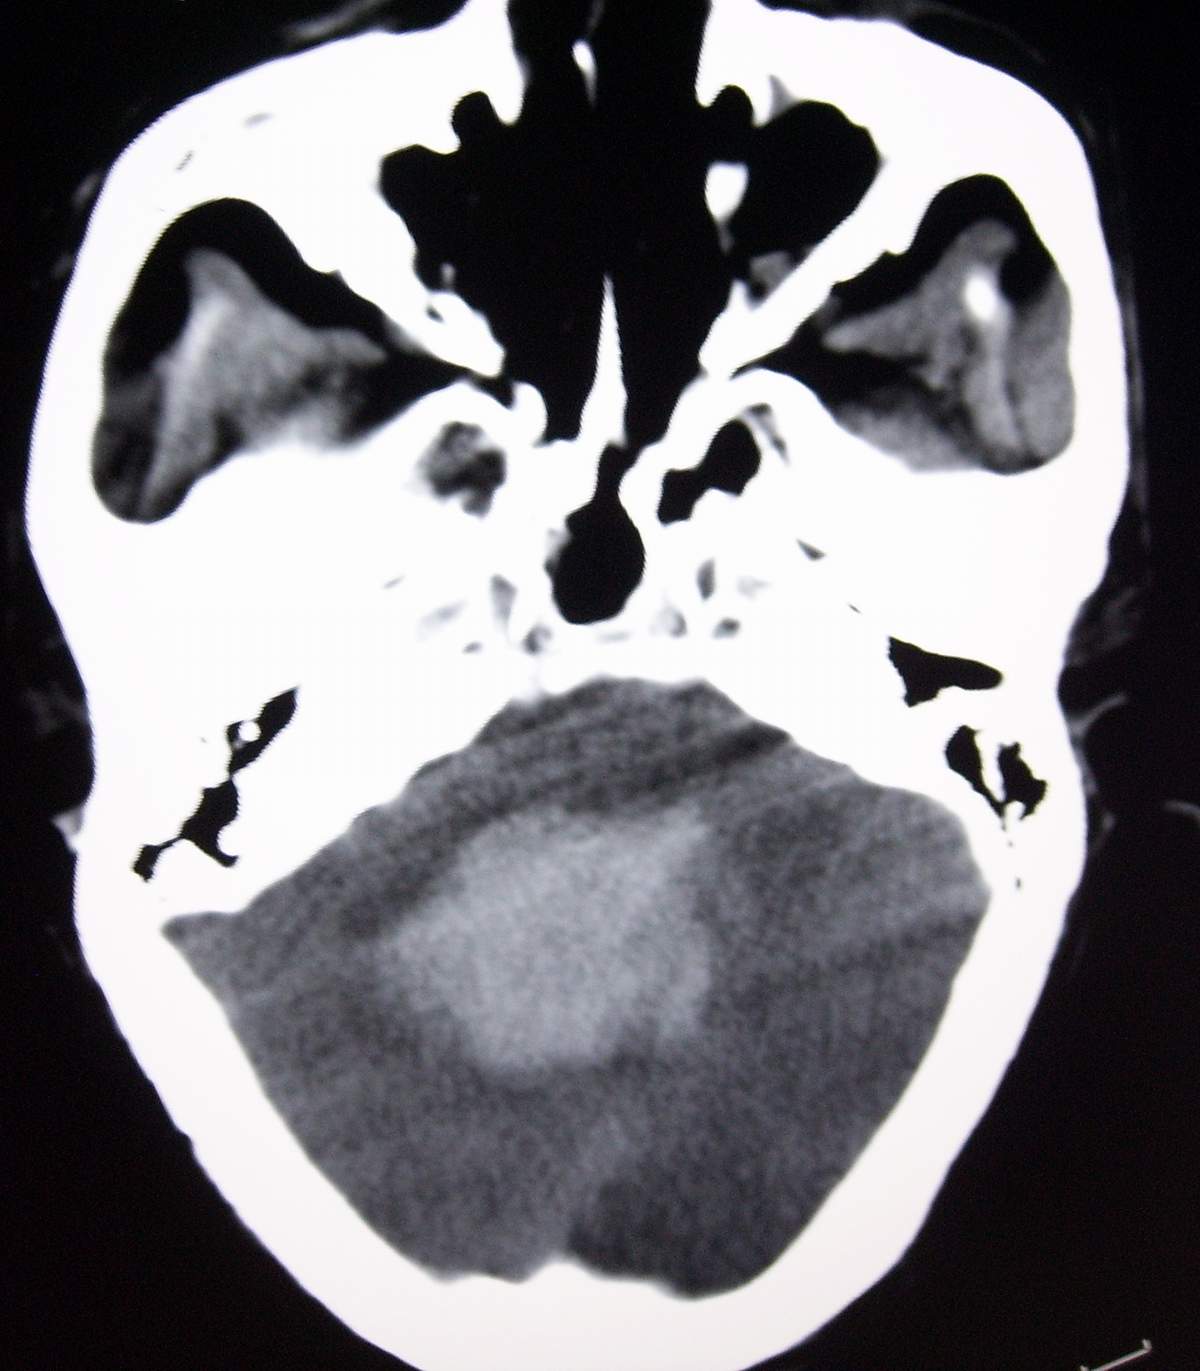

男,55岁,突然不省人事2小时。

小脑出血破入脑室

小脑出血,蛛血

还是支持第四脑室出血可能性大。蛛网膜下腔出血。

考虑脑桥基底部原发性脑出血并破入中脑导水管、四脑室及蛛网膜下腔。

支持右侧小脑半球原发性脑出血破入脑室系统、蛛网膜下伴急性梗阻性脑积水。

右侧小脑出血并破入脑室系统、蛛网膜下腔

考虑小脑出血破入脑室系统,蛛血.

考虑小脑出血并破入脑室,急性梗阻性脑积水;

支持小脑蚓部出血伴脑室及蛛网膜下腔积血。脑积水。进一步查因。